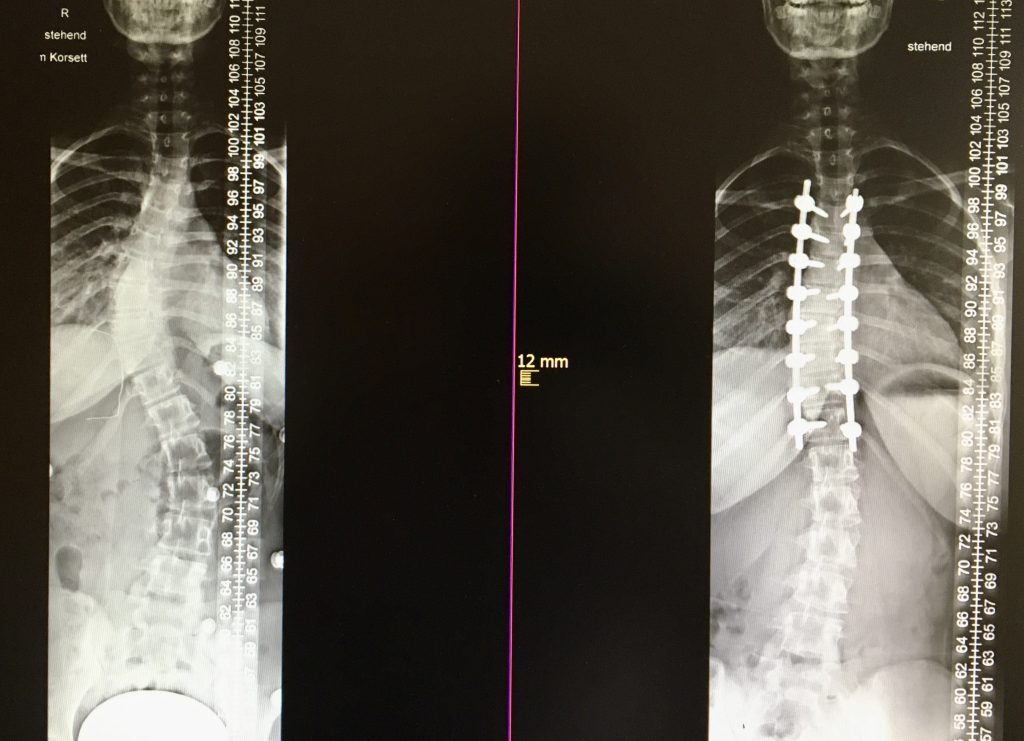

Habitualmente la escoliosis se corrige por vía posterior con monitorización de la función nerviosa durante la intervención (neurofisiología intraoperatorios). Se colocan tornillos en las vértebras y se acoplan con barras de metal a cada lado de la columna, tras realizar las maniobras de corrección necesarias, se consigue de este modo estabilizar el raquis y una columna vertebral más equilibrada y de aspecto más recta. Lo más habitual es utilizar técnicas de fusión ósea mediante el aporte de injerto de hueso del propio paciente o material sustitutivo al lecho quirúrgico. Este proceso se denomina fusión espinal. Las barras de metal acopladas a la columna vertebral aseguran que la columna permanezca recta mientras se produce la fusión espinal.

Los pacientes pueden necesitar estancia en UCI para optimizar el manejo posoperatorio durante las primeras 24 horas. A partir de ahí el posoperatorio no difiere del de una fusión espinal normal, siendo la estancia hospitalaria entre 5-7 días.

Algunos pacientes pueden regresar al colegio o al trabajo en un período de 2 a 4 semanas después de la cirugía y reanudar muchas actividades de la vida cotidiana en 4 a 6 meses. Después del proceso de recuperación, es posible que los pacientes puedan volver a llevar una vida activa normal.